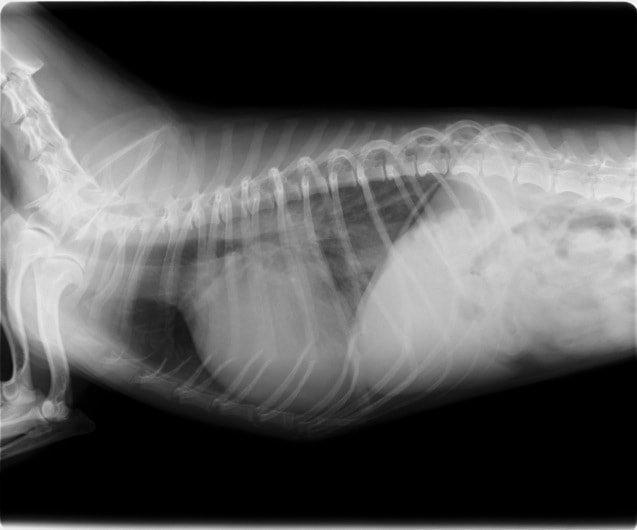

症例1:【マルチーズ 12歳齢 去勢オス】

B:胸部レントゲン写真 側面像

胸部レントゲン検査において重度の心拡大と肺水腫が認められた。超音波検査では、重度の僧帽弁閉鎖不全症、三尖弁閉鎖不全症、中程度の大動脈弁閉鎖不全症を合併していることが判明した。三尖弁逆流速度から肺高血圧症が示唆された。